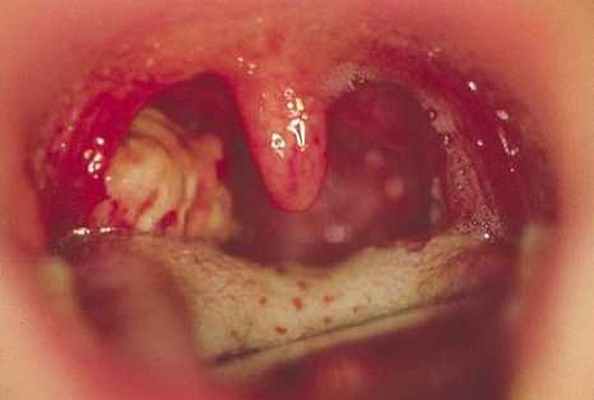

Ангина при брюшном тифе • Клиническая картина •• Как начальный симптом заболевания ангина возникает в 50-70% случаев •• В продромальном периоде — подъём температуры тела •• Умеренная боль в глотке •• Лимфатические узлы увеличены на стороне поражения, болезненны при пальпации • Фарингоскопия: в начале заболевания — картина катаральной ангины, затем на 2-й неделе может возникнуть одностороннее безболезненное язвенно-некротическое поражение миндалины с образованием на ней мелких округлых язвочек с гладкими красными краями и сероватым дном, распространяющихся на нёбные дужки. Через 4 нед появляются участки грануляционной ткани с последующей эпителизацией.

В первые дни заболевания у больных брюшным тифом или паратифами (инфекционное заболевание, которое вызывает микроорганизм сальмонелла) А и В, отмечают умеренные боли в глотке, кратковременной повышение температуры и явления, характерные для острого катарального тонзиллита. На 2 неделе возможно язвенно-некротическое изменение в миндалинах: образуются мелкие язвочки округлой формы с гладкими краями красного цвета и бело-серым дном. Эти язвочки распространяются на небные дужки.

Изменения в миндалинах сопровождаются ипсилатеральным (расположенным на той же стороне) увеличением в размерах регионарных лимфатических узлов, которые при пальпации достаточно болезненны. Зоны некротизации (отмирания), которые имеются на нёбных миндалинах, на третьей неделе заболевания начинают очищаться, а на четвертой - появляются участки с грануляционной тканью и происходит процесс эпителизации (самопроизвольное закрытие ран).

Ангина Дюге

Дюге ангина (J.В.N.Duguet, 1837-1914, франц. врач) - набухание небных миндалин и дужек с появлением на них мелких округлых язвочек с серовато-белым цветом дна, иногда наблюдающееся при брюшном тифе.